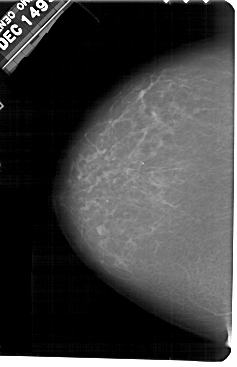

A_1601_1.RIGHT_MLO

RIGHT_MLO LINES 5461 PIXELS_PER_LINE 3601 BITS_PER_PIXEL 12 RESOLUTION 43.5 OVERLAY

FILE: A_1601_1.RIGHT_MLO.OVERLAY

TOTAL_ABNORMALITIES 1

ABNORMALITY 1

LESION_TYPE CALCIFICATION TYPE PLEOMORPHIC DISTRIBUTION LINEAR

ASSESSMENT 4

SUBTLETY 2

PATHOLOGY BENIGN

TOTAL_OUTLINES 1

BOUNDARY